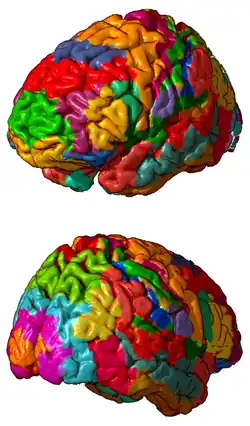

Áreas de Brodmann

Un área de Brodmann es una región de la corteza cerebral definida con base en su citoarquitectura.

La citoarquitectura de la corteza cerebral es la disposición de los somas de las neuronas que constituyen la corteza cerebral. Brodmann el neurólogo alemán, postuló áreas funcionales, basado solamente en la arquitectura histológica microscópica.

Las áreas de Brodmann fueron definidas y numeradas de la 1 a la 47 por Korbinian Brodmann en 1909 usando la tinción de Nissl.

Los primeros mapas fueron de humanos y monos entre otros, algunas de estas áreas fueron subdivididas, como por ejemplo la 23, que se divide en 23a y 23b.